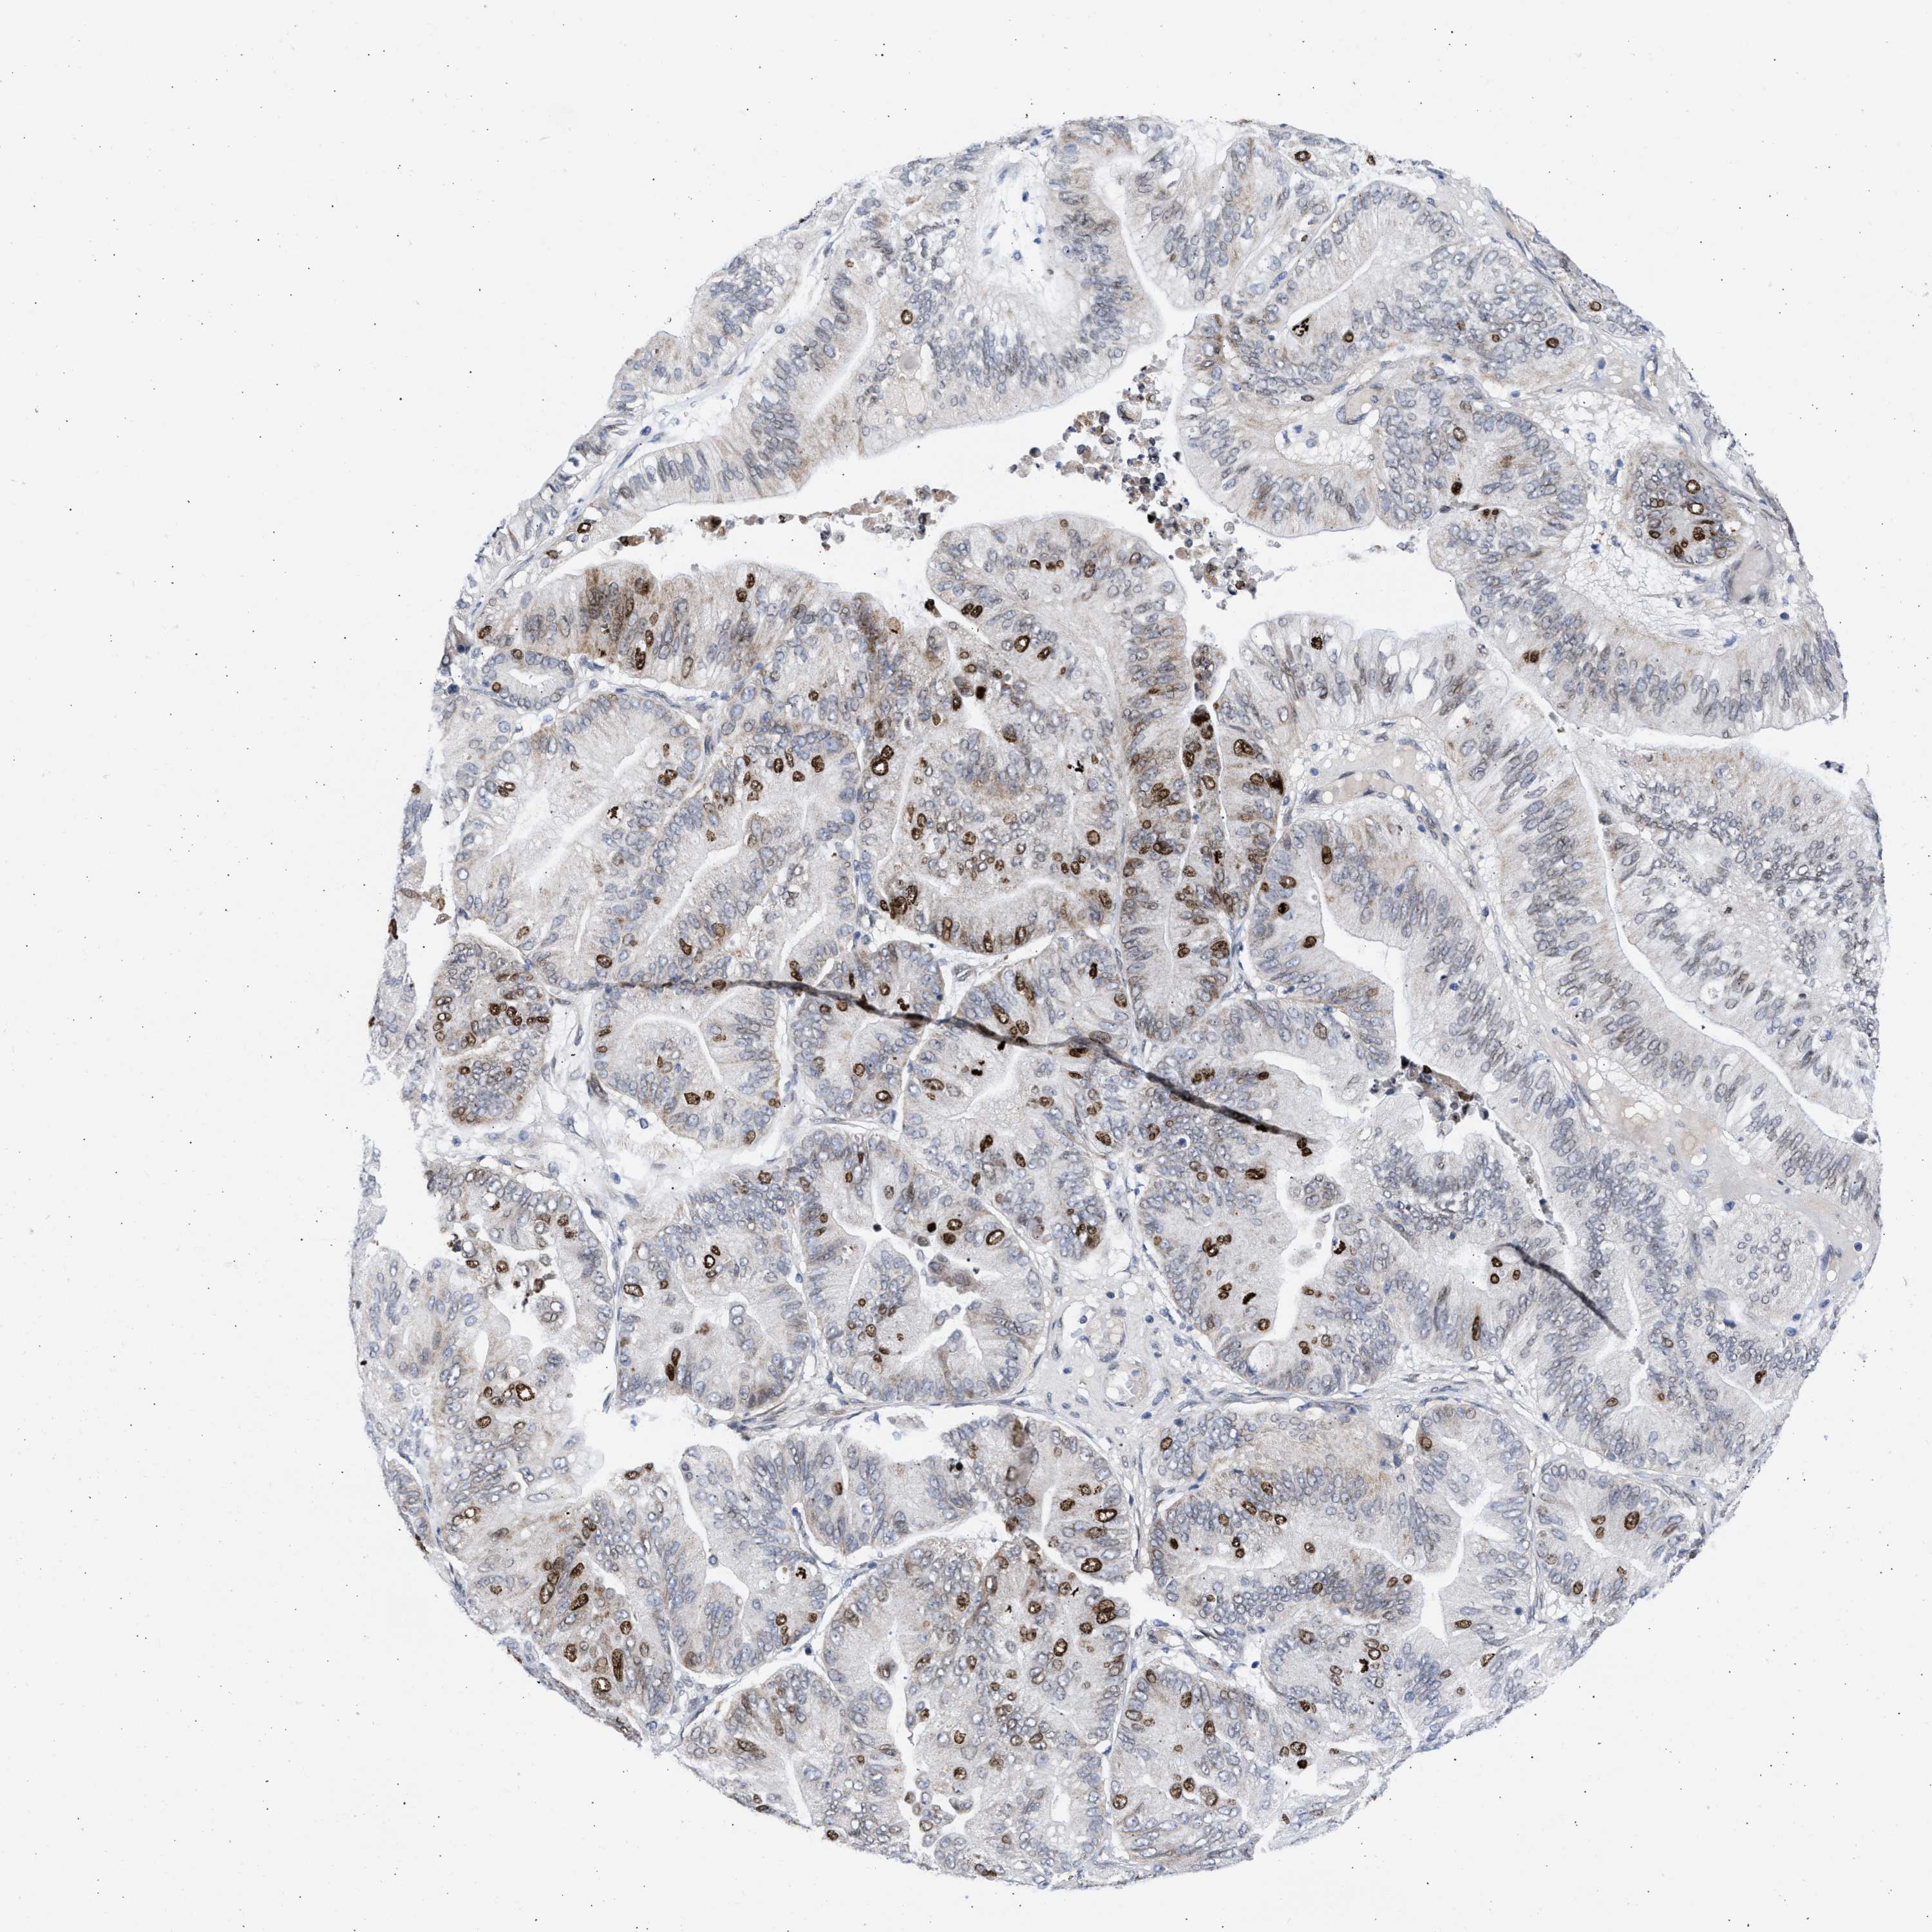

OVARIAN CANCER - Protein expressioni

A mouse-over function shows sample information and annotation data. Click on an image to view it in a full screen mode. Samples can be filtered based on level of antibody staining by selecting one or several of the following categories: high, medium, low and not detected. The assay and annotation is described here.

Note that samples used for immunohistochemistry by the Human Protein Atlas do not correspond to samples in the TCGA dataset.

Antibody stainingi

Antibody staining in the annotated cell types in the current human tissue is reported as not detected, low, medium, or high, based on conventional immunohistochemistry profiling in selected tissues. This score is based on the combination of the staining intensity and fraction of stained cells.

Each image is clickable and will lead to virtual microscopy that enables deeper exploration of all samples and also displays staining intensity scores, fraction scores and subcellular localization as well as patient and tissue information for each sample.

Antibody HPA018401

Antibody HPA018410

Antibody HPA018441

Staining

High

Medium

Low

Not detected

Intensity

Strong

Moderate

Weak

Negative

Quantity

>75%

75%-25%

<25%

None

Location

Nuclear

Cytoplasmic/membranous

Cytoplasmic/membranous,nuclear

Cystadenocarcinoma, serous, NOS

Carcinoma, endometroid

Cystadenocarcinoma, mucinous, NOS

Carcinoma, NOS